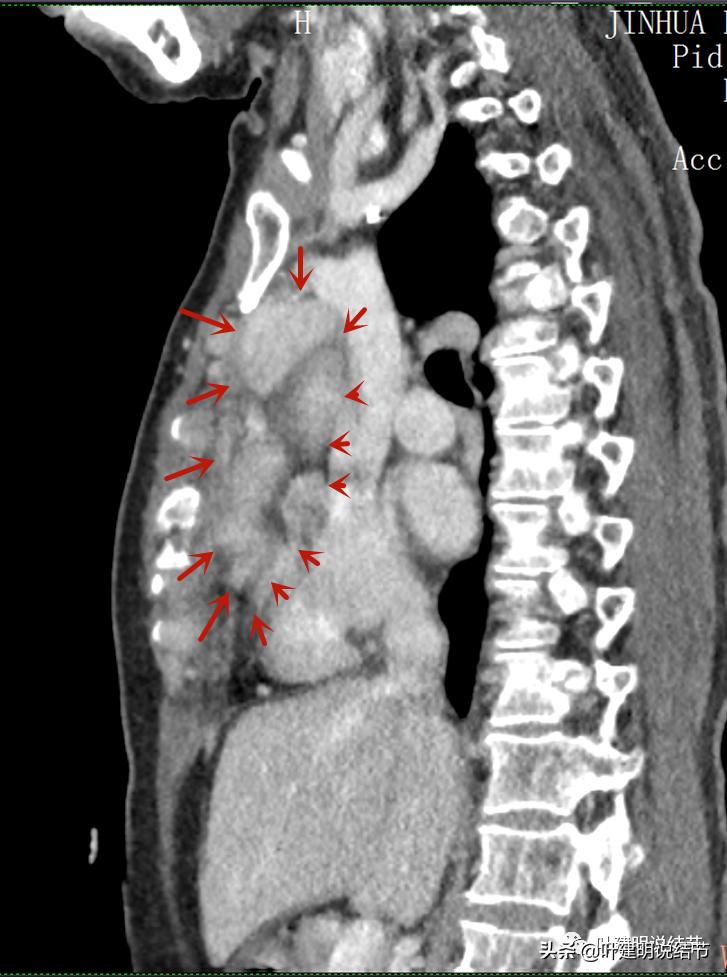

再来看看她的CT增强图像:

以下图片左侧是肺窗,右侧是纵隔窗。红色箭头示病灶,桔色箭头示无名静脉,黄色箭头示支气管,砖色箭头示上腔静脉,蓝色箭头示主动脉,紫色箭头示肺动脉。

病灶之间似不相连的,矢状位上见从上到下延续的

病灶占据前纵隔从上到下全程,多中心,密度不均,对心脏与大血管有压迫,没有明显侵犯

病灶表面不平,中间有坏死